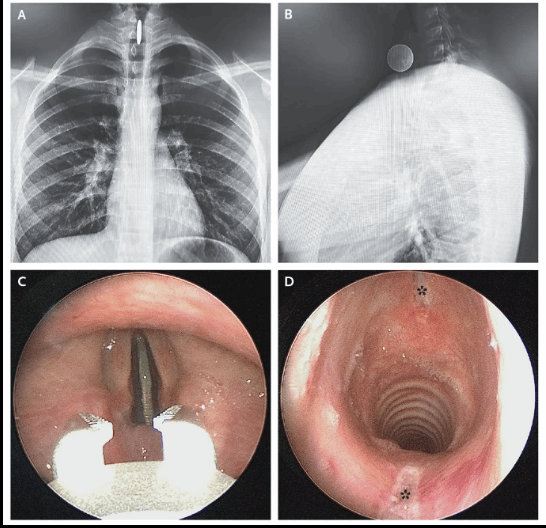

طفل ابتلع 25 سنتاً... وهذه كانت النتيجة! (صور)

طفل ابتلع 25 سنتاً... وهذه كانت النتيجة! (صور)